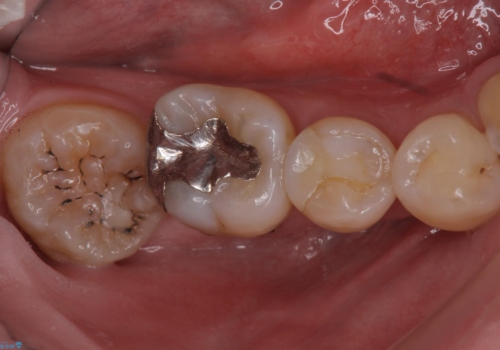

詰め物の下が虫歯 つぎはぎの歯をしっかり治療

詰め物の下が虫歯になっていました。

虫歯をしっかりとった後、セラミックで修復しました。

詰め物の下の虫歯は特に奥歯は大きかったのですが、神経を取らずに済みました。